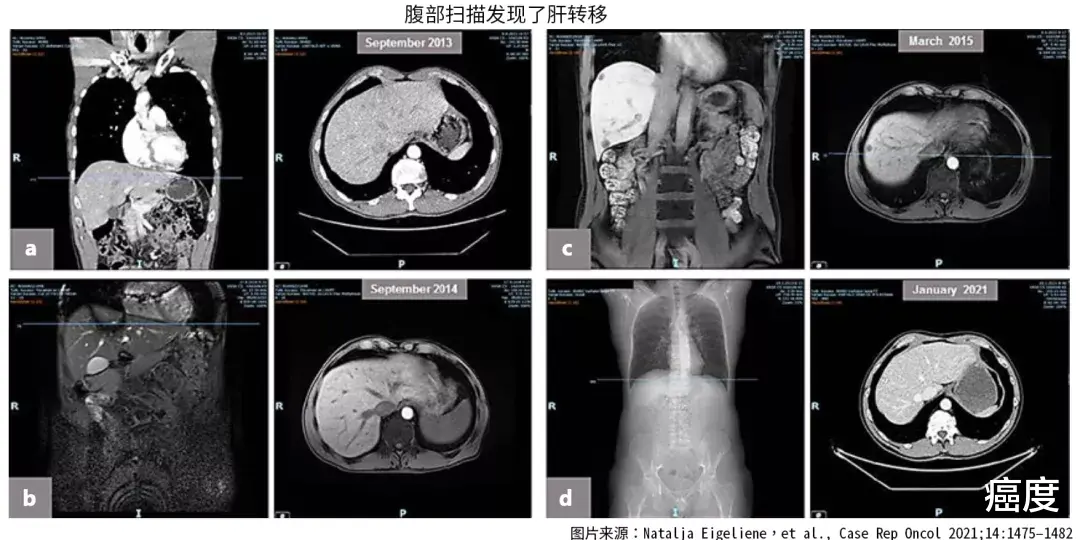

图1.治疗不同阶段的肝部影像学检查

2013年10月 , 患者进行了腹腔镜辅助腹会阴切除术 , 手术后7天 , 发生了急性肠梗阻 。 为此进行了剖腹探查 , 对导致梗阻的肿瘤进行了清除 。 患者的直肠系膜筋膜完整 , 但是有淋巴浸润 , 且存在不可手术切除的肝转移 , 肝内没有胆汁淤积的迹象 。 肝功能检查转氨酶、胆红素等都在参考值之内 。 血常规的血红蛋白、白细胞和血小板也都在参考值之内 。

2014年3月 , 经检查发现肝部病灶达到了完全缓解 , 也就是肝部的转移灶都消失了 。

2015年3月 , 在暂停治疗9个月后 , 核磁观察到肝内的转移灶出现了复发 。 活检证实为肠癌转移病灶 。 为此进行了一个周期的帕尼单抗联合卡培他滨的新辅助治疗 , 并进行了肝部转移灶的切除 。

2021年1月 , 最后一次的随访复查 , 也没有再次发现复发的迹象 。 肿瘤标志物都在参考值之内 。 从发现疾病至今已经过去9年了 。